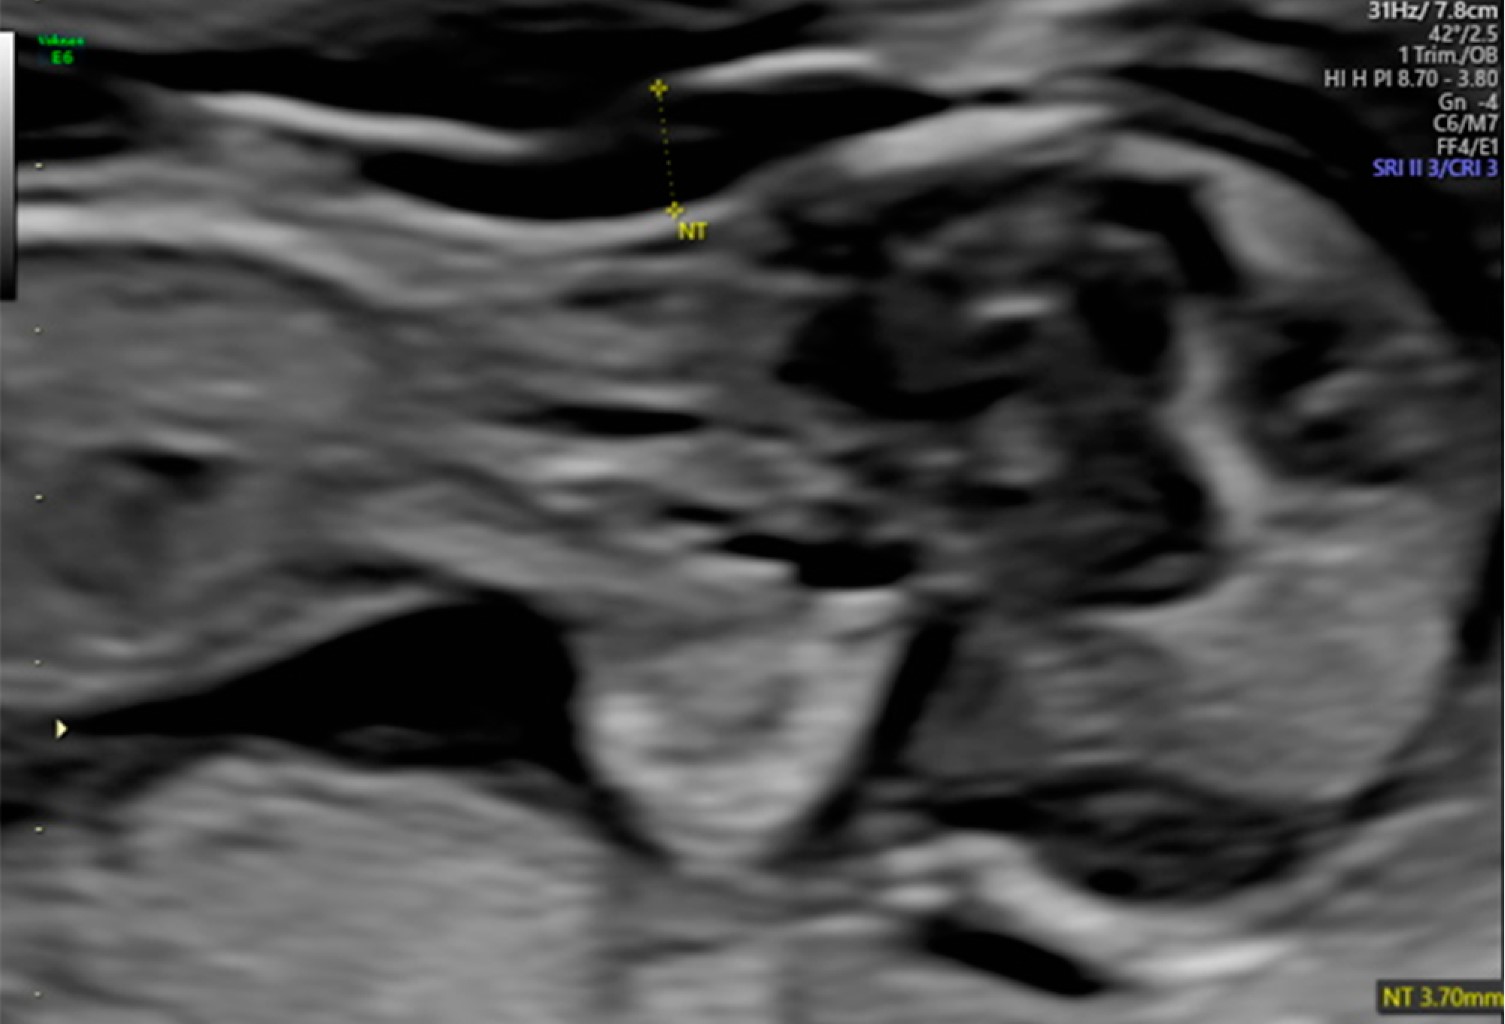

Tiene una frecuencia de 1 en cada 10,000 recién nacidos vivos y tiene gran relevancia dado que se asocia con malformaciones cardiacas y abdominales, las cuales se deben diagnosticar de manera prenatal a través del ultrasonido de tamizaje del primer trimestre del embarazo (Figura 3). Se debe emplear el Doppler color para la confirmación de cardiopatías. En este síndrome se agrupan variantes y diferentes grados de afectación (Figura 4).

Figura 3